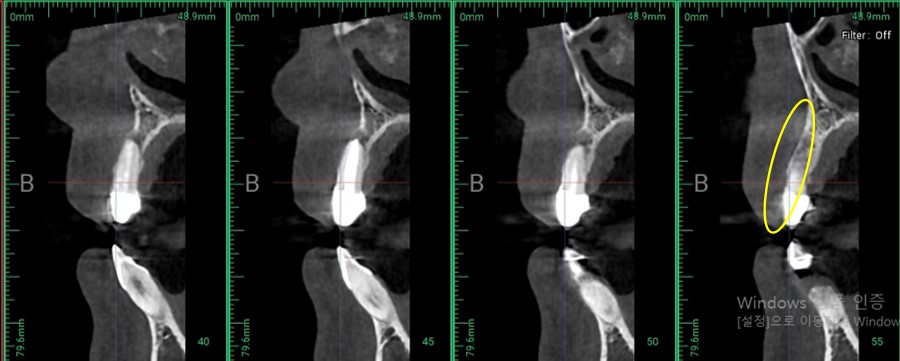

이 환자분은 ct 사진을 보시면 알 수 있듯이 뼈 자체가 워낙 얇고 없는 편 이였습니다.

▲ CT 사진

지금 보시는 ct 사진은 환자분을 측면으로 보는 모습인데요

잇몸 뼈가 많이 얇기도 했지만 낭종으로 인해 잇몸뼈가 소실된 모습입니다.